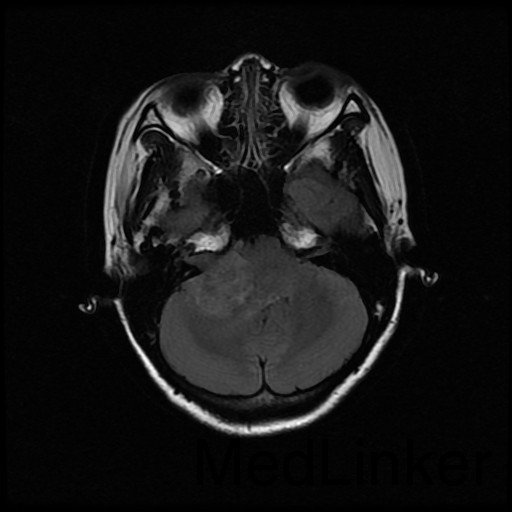

主诉:双眼视物模糊2月余 病史:中年女性,慢性病程。2月前无明显诱因出现双眼视物模糊,当地医院MRI提示:右侧桥小脑角处异常信号,占位,脑膜瘤?胶质瘤?血管母细胞瘤?建议增强扫描。

查体:神志清醒,查体合作。双眼视物模糊,眼球运动无明显异常。双侧瞳孔等大等圆,直径3mm,对光反射灵敏。 辅查:头部CT示:右侧桥小脑角区占位,考虑听神经瘤可能,并梗阻性脑积水。建议进一步MRI检查;头部MR示:右侧桥小脑角区占位,考虑为听神经瘤,并梗阻性脑积水;DTI示脑桥、桥臂及右侧桥小脑角白质纤维束受压移位。

随访:术后病理结果提示:(右侧桥小脑角处肿物)肿瘤由梭形细胞构成,可见疏区及密切,部分细胞呈栅栏状排列,细胞有异型性,核分裂可见,间质有散在淋巴细胞浸润,结合免疫组化结果,符合神经鞘瘤。 讨论:听神经瘤是桥小脑区最常见的肿瘤,也是最常见的脑神经瘤,绝大多数病理类型为神经鞘瘤。下面结合本例影像学习一下其影像表现:首先就是部位,发生于桥小脑区的占位第一反应是听神经瘤,而且和岩骨是呈锐角相交,该征象可以和发生于该部位脑膜瘤鉴别。另外,肿瘤沿听神经长如,导致内听道扩大也是一个重要征象。增强扫描可见明显强化,这可以和发生于该部位的胆脂瘤鉴别。